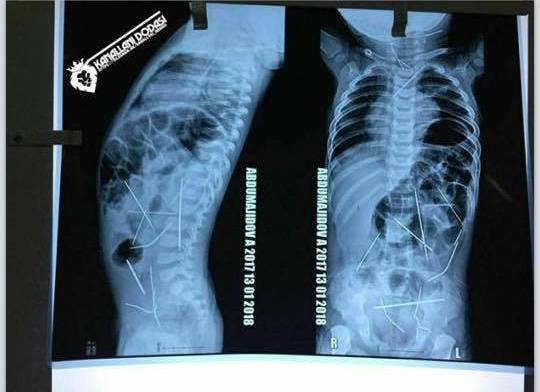

Узбекские врачи продолжают бороться за жизнь 11-месячного малыша, в теле которого обнаружили 16 иголок, сообщает NUZ.UZ.

По словам директора Республиканского научного центра экстренной медпомощи Асилбека Худаярова, состояние мальчика оценивается как крайне тяжелое. "Операция была очень сложная. Ребенок несколько часов провел под наркозом. Кроме того, он несколько месяцев жил с инородными телами, которые, естественно, не были стерильными. Все это время организм как мог боролся, поэтому у пациента была диагностирована выраженная интоксикация. Да, пока проведена только одна операция. Несколько игл все еще остаются в теле мальчика.

Я постараюсь объяснить: в медицинской практике есть два понятия - абсолютные показания и относительные показания. То, что врачи извлекли те иглы, которые угрожали жизни пациента, - это абсолютные показания. То, что в теле малыша осталось несколько игл, не угрожающих жизни, мы считаем относительными показаниями. Оставшиеся иголки находятся в таких местах, что во время удаления может возникнуть нарушение целостности какого-то жизненно важного органа. Поэтому пока остановились и оставили в таком состоянии", - прокомментировал представитель больницы.

В настоящее время ведется доследственная проверка и отрабатываются все возможные версии. По предварительным данным, иглы попали в тело ребенка через кожу. Об этом изначально заявил хирург, проводивший сложнейшую операцию.